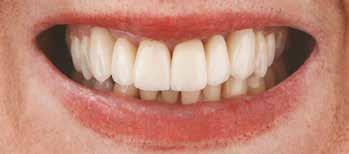

Kiindulási helyzet

A páciens egy 56 éves nőbeteg, nem dohányzik, általános egészségi állapota jó (ASA I), gyógyszert nem szed, ismert allergiája nincs. Fő panasza, amellyel klinikánkat felkereste, hogy elégedetlen mosolyával. Elmondása alapján az utóbbi években krónikus gyulladás alakult ki frontfogai körül, amely érezhető mobilitáshoz vezetett. Ez a probléma jelentősen befolyásolta a magabiztos beszédben és étkezésben. A páciens hosszú távú megoldást keresett, de aggódott a kezelések alatt fellépő esetleges fájdalom miatt. Az extraorális vizsgálat során megállapítottuk, hogy a mosolyvonal közepesen magas és a frontfogak torlódottak (1–2. ábrák). A szájüregi vizsgálat során a 1.2, 2.1 és 2.2 fogak körül előrehaladott parodontális tapadásveszteséget és mobilitást találtunk (3. ábra). A CBCT (cone beam CT) felvételen látszott, hogy a 2.1 fog bukkális csontfala hiányzik (4. ábra).

1. ábra: Az extraorális vizsgálat közepesen magas mosolyvonalat mutatott.

2. ábra: A torlódott felső frontfogak.